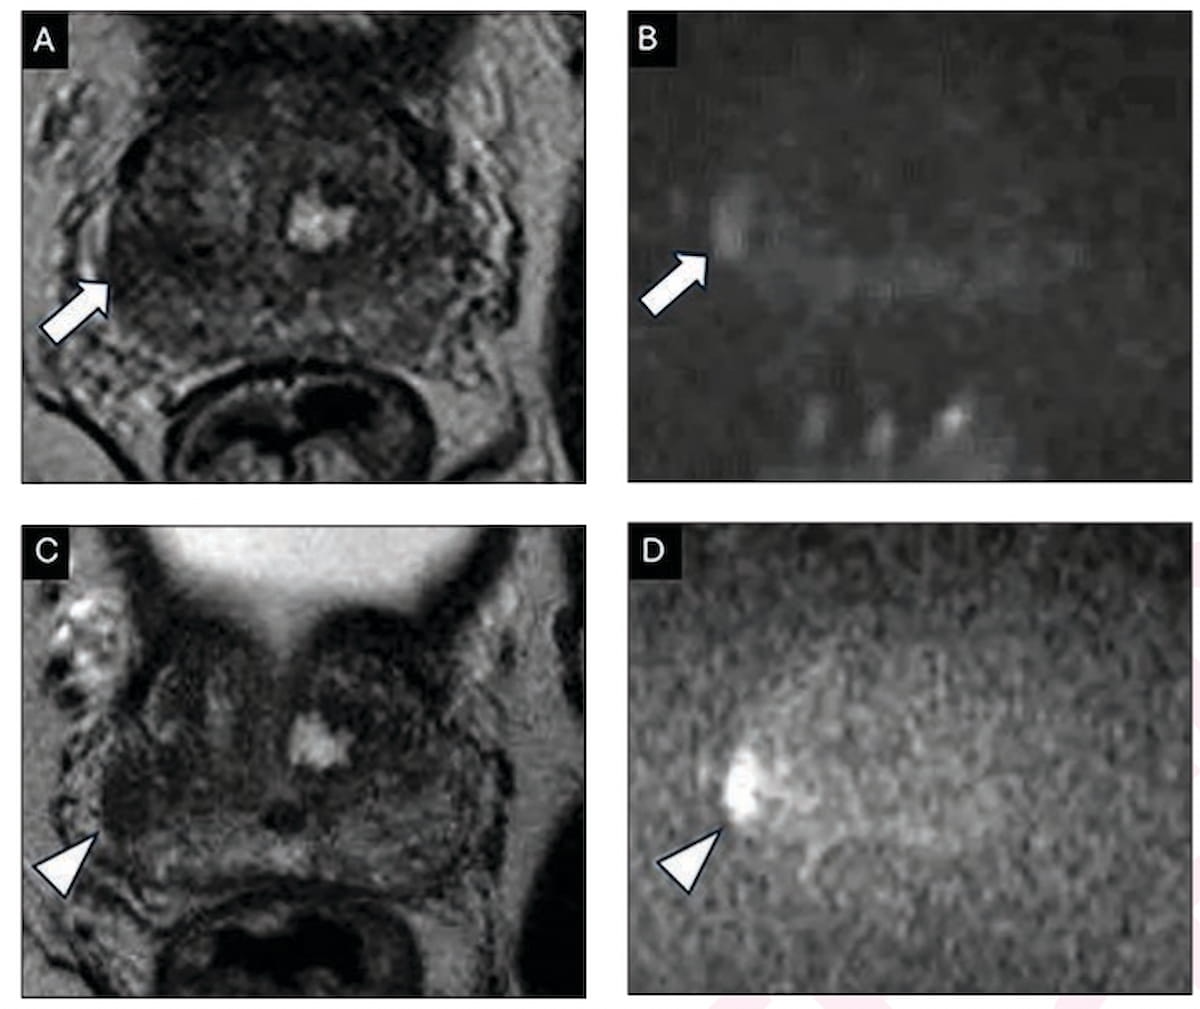

The use of 68Ga-RM2 PET/MRI demonstrated a 35 percent higher sensitivity rate than MRI alone for the diagnosis of biochemical recurrence of prostate cancer, according to research recently presented at the Radiological Society of North America (RSNA) conference.